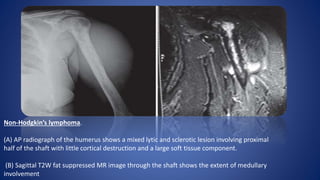

Non-Hodgkin’s lymphoma.

(A) AP radiograph of the humerus shows a mixed lytic and sclerotic lesion involving proximal

half of the shaft with little cortical destruction and a large soft tissue component.

(B) Sagittal T2W fat suppressed MR image through the shaft shows the extent of medullary

involvement